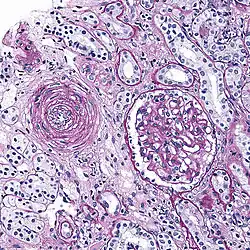

Micrograph showing hyaline arteriolosclerosis in the kidney. PAS stain.

Hyaline arteriolosclerosis

Also arterial hyalinosis and arteriolar hyalinosis refers to thickening of the walls of arterioles by the deposits that appear as homogeneous pink hyaline material in routine staining.[3] It is a type of arteriolosclerosis, which refers to thickening of the arteriolar wall and is part of the aging process.[4]

"Onion-skin" renal arteriole

This is a type of arteriolosclerosis involving a narrowed lumen.[4] The term "onion-skin" is sometimes used to describe this form of blood vessel[14] with thickened concentric smooth muscle cell layer and thickened, duplicated basement membrane. In malignant hypertension these hyperplastic changes are often accompanied by fibrinoid necrosis of the arterial intima and media. These changes are most prominent in the kidney and can lead to ischemia and acute kidney failure. In the brain, a small cavity called a lacune is an ischemic cavity that can arise due to brain necrosis, due to arteriolosclerosis.[15][16]